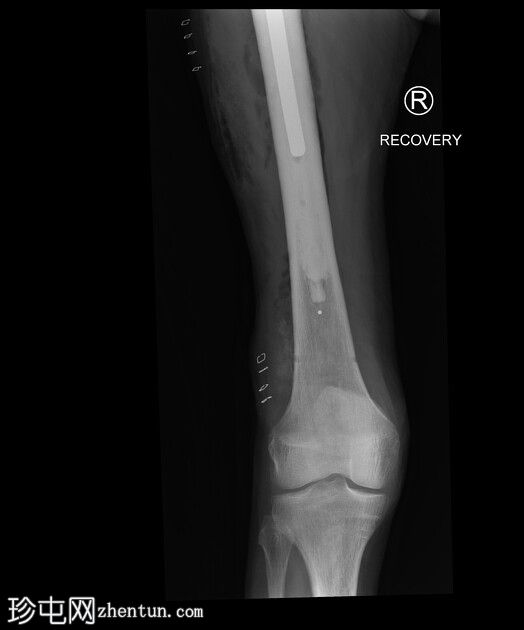

X 光片

7.png

正面

8.png

侧位

9.png

术中恢复期影像学检查:股骨髓内钉固定穿过小转子水平处已知的溶骨性病变。无金属部件损坏或假体周围骨折。